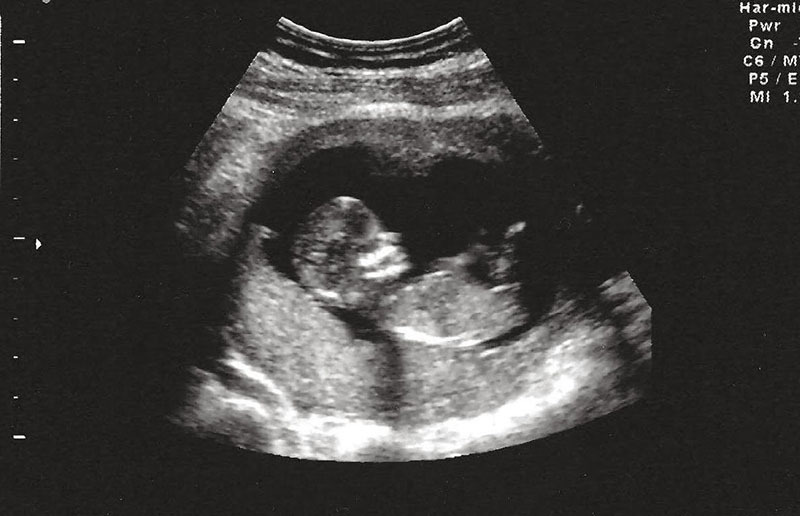

Siêu âm có thể giúp chẩn đoán tình trạng khối u của thai nhi từ trong bụng mẹ